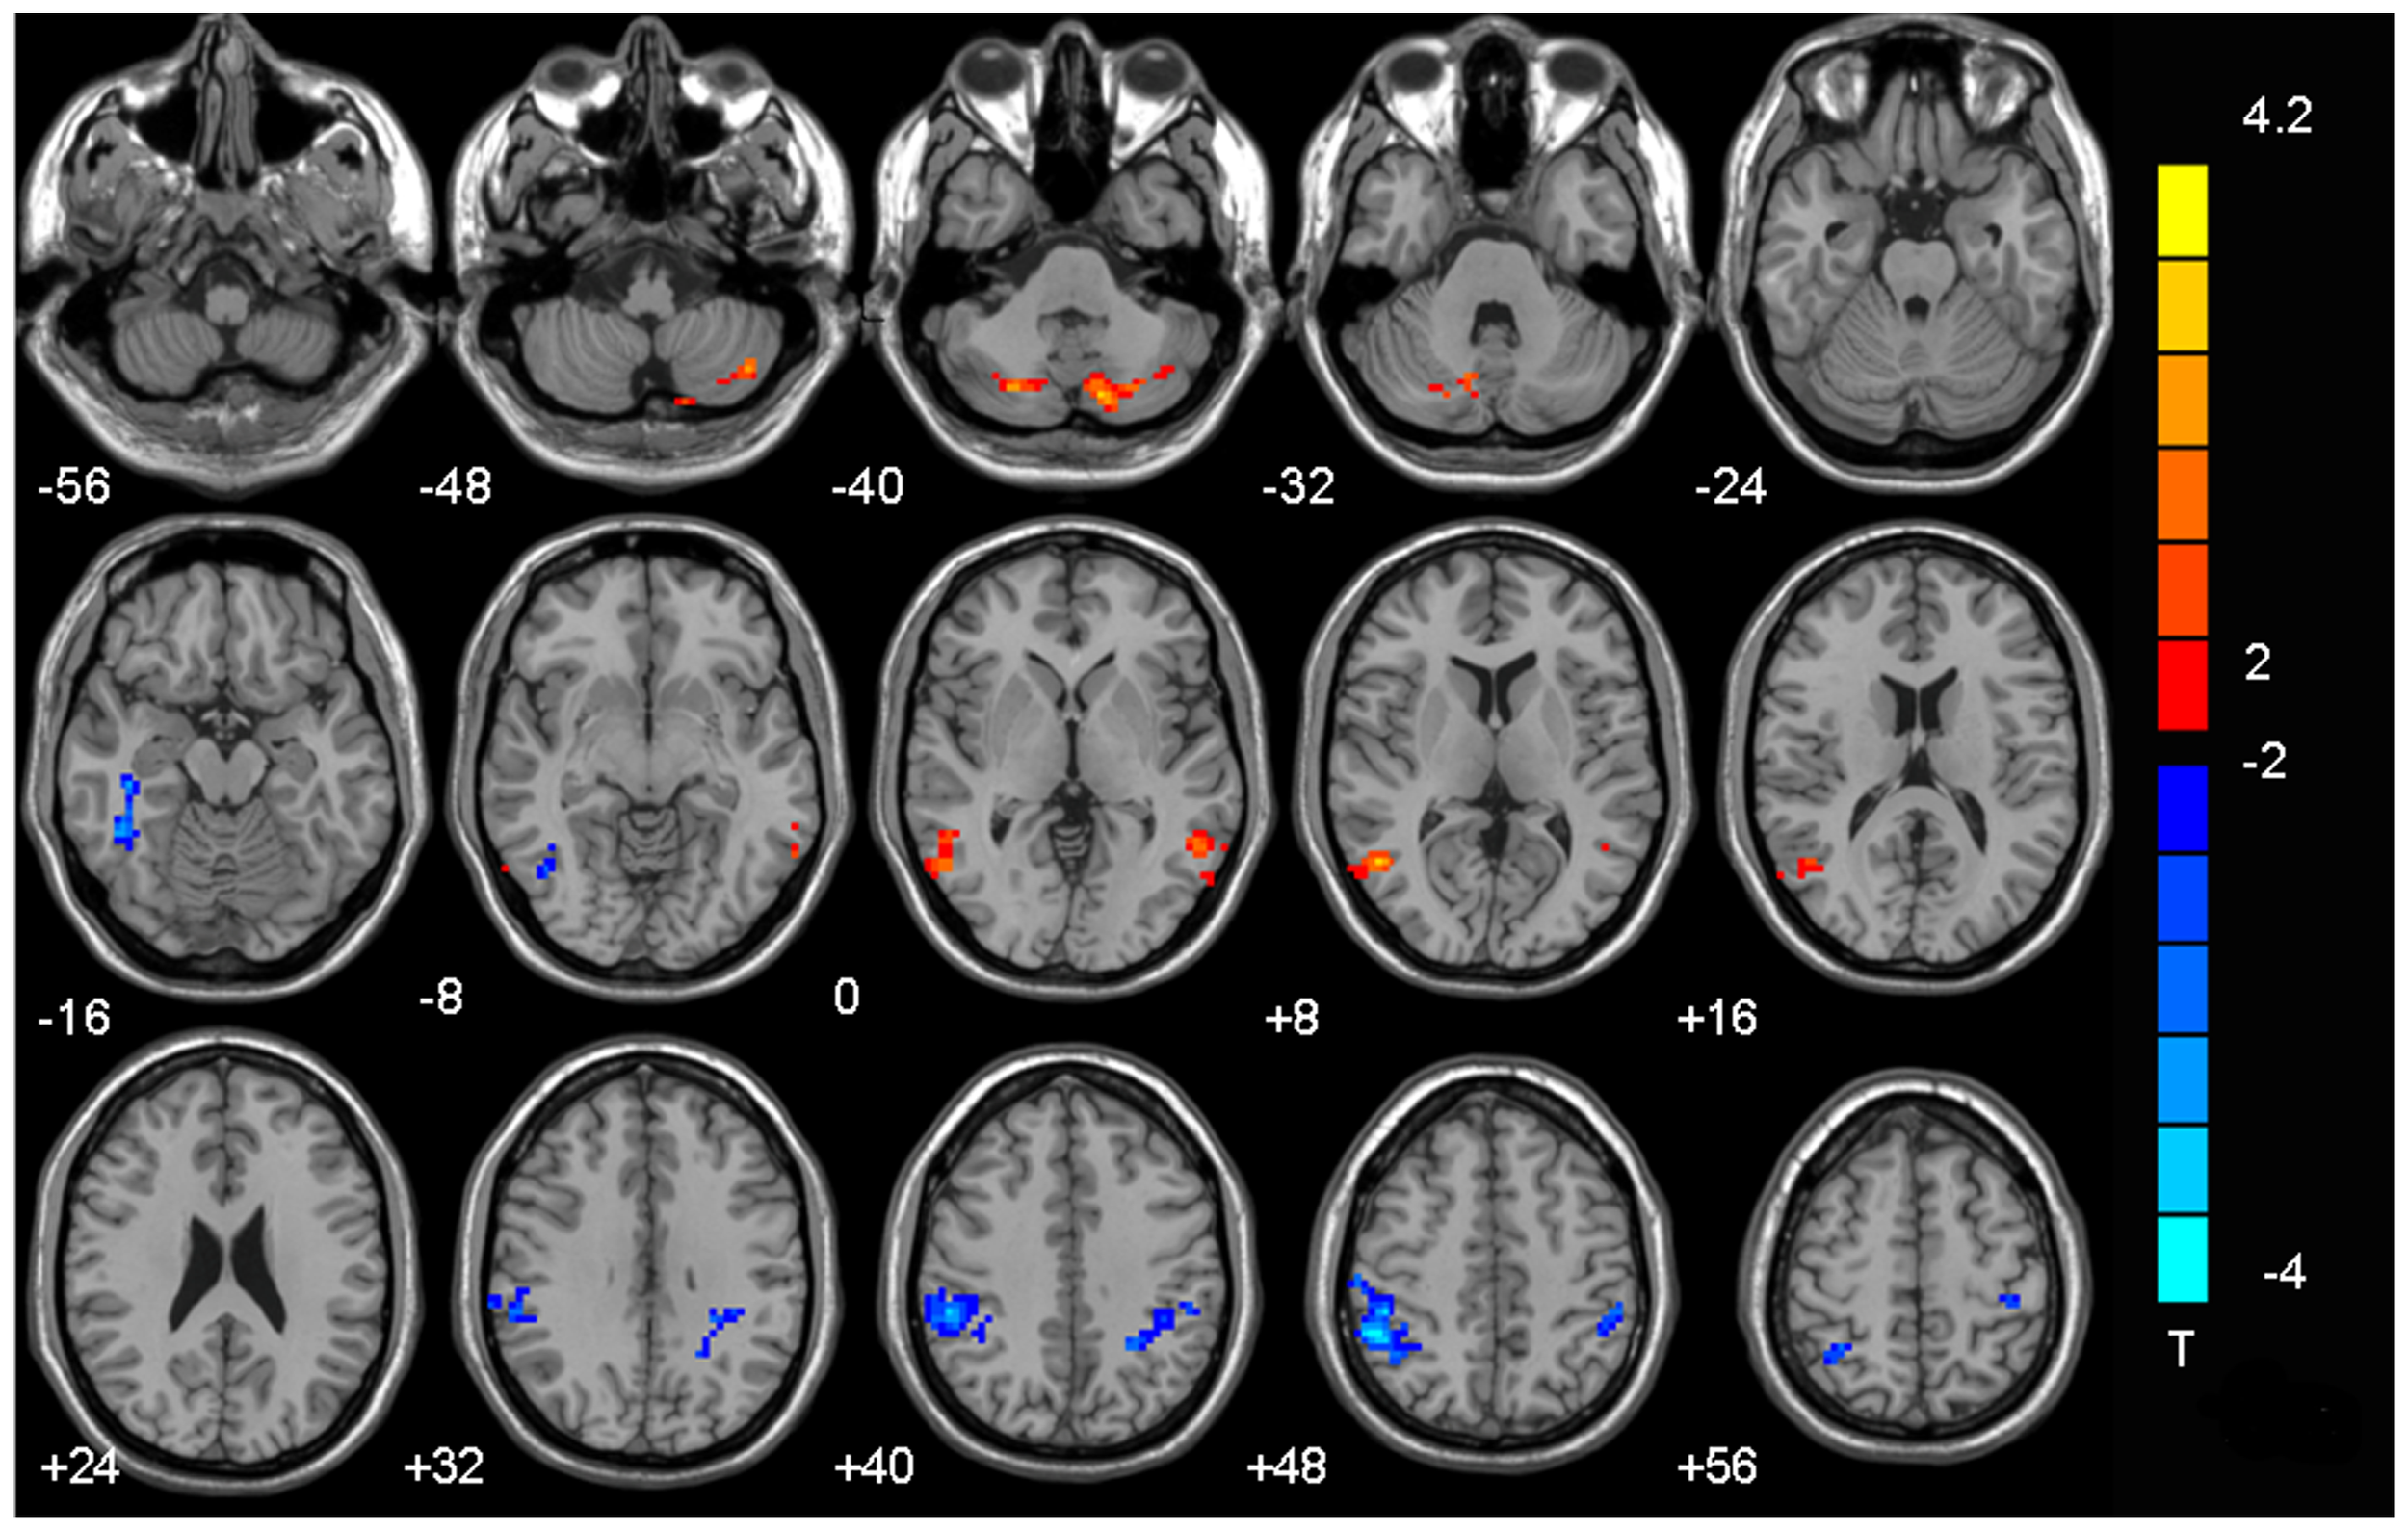

Figure 1.0

This brain scan compares teenagers with heavy internet gaming habits to those without. The coloured areas show significant differences in brain connections. Red areas indicate where teens with heavy gaming have increased brain connectivity, suggesting strengthened neural pathways related to habits, impulsive actions, and reward-seeking. Blue areas highlight decreased connectivity in these teens, suggesting weakened brain connections in regions responsible for attention, impulse control, and cognitive efficiency. Simply put, the red dots point to brain areas becoming overly active and impulsive, while the blue dots show areas becoming less effective at maintaining focus and control (Hong et al., 2013).